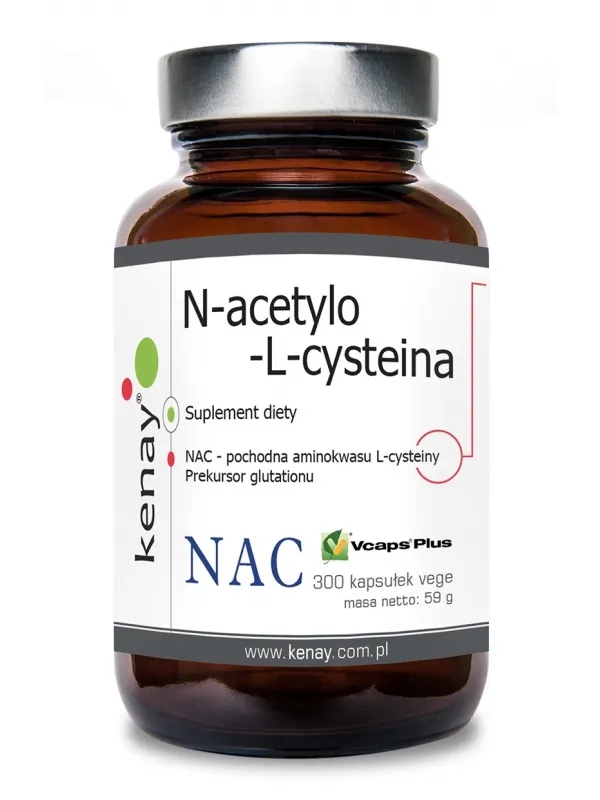

NAC suplement co to jest i jak może poprawić Twoje zdrowie